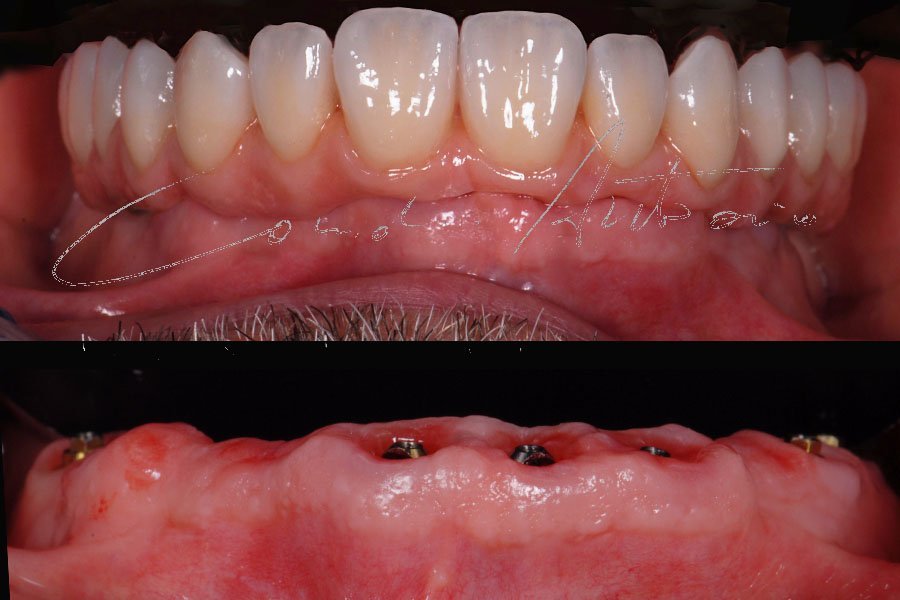

Complete Digital Patient (CDP): guided surgery for complete upper and lower rehabilitation with zirconia-ceramic screw-retained implants

Complete Digital Patient (CDP): the use of guided surgery for implant restoration in total upper and lower rehabilitation with titanium bars and different types of zirconia-ceramic

Full upper and lower rehabilitation with titanium and zirconia bars

Upper and lower prosthetic rehabilitation with titanium bars and translucent zirconia-ceramic structures. The CDP as an aid in communication between the entire team and the patient, who is the focus of the work.